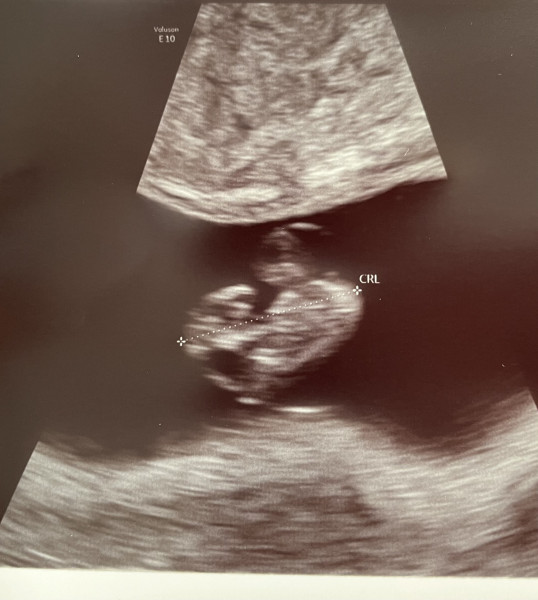

@tasha4eva10 it's easy how tiny they are! According to my app baby should be just over 3cm (about the size of an olive) so maybe! Still tiny though! My tummy on the other hand is not looking so small anymore 😅

I am 8 +3 today. Got my reassurance scan yesterday. Little one is looking healthy 😌. Anyone has suggestions what kind of test should be done when exactly ? Just conscious not to miss any deadline.

Hope you're all doing well 🥰 11+3 today and exhausted!

Evening ladies, how is everyone doing today? Well we have our first private scan tomorrow morning and partner has tested positive for covid 🙈. For those who have had private scans before do you think they will be ok with me FaceTiming him during the scan so he doesn't miss out? I'm really nervous now about the scan I don't remember being this nervous with my first! I'm having lots of symptoms and have a bump so there's no reason to think otherwise but the anxiety is real!

My scan can't come around quickly enough for me! Not got any anxiety or anything like that, I just can't keep it a secret from family any longer 🤣 I've got a definite bump now so have to wear baggy jumpers every time I go out in case I bump into someone! 🤦‍♀️